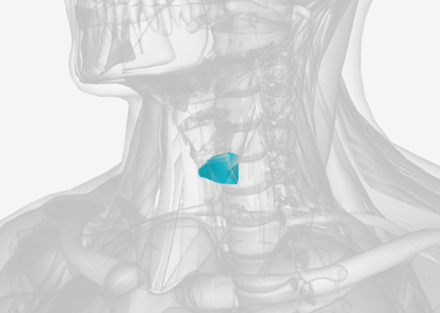

Cricopharyngeus

origin is the cricoid cartilage, coursing back to the orifice of the esophagus; function is to constrict the superior orifice of the esophagus; also referred to as the upper esophageal sphincter

Cricopharyngeus

|  |  |

Cricopharyngeus

F

Upper Esophageal Sphincter

Also know as the cricopharyngeus

cricopharyngeus

Also known as Upper Esophageal Sphincter